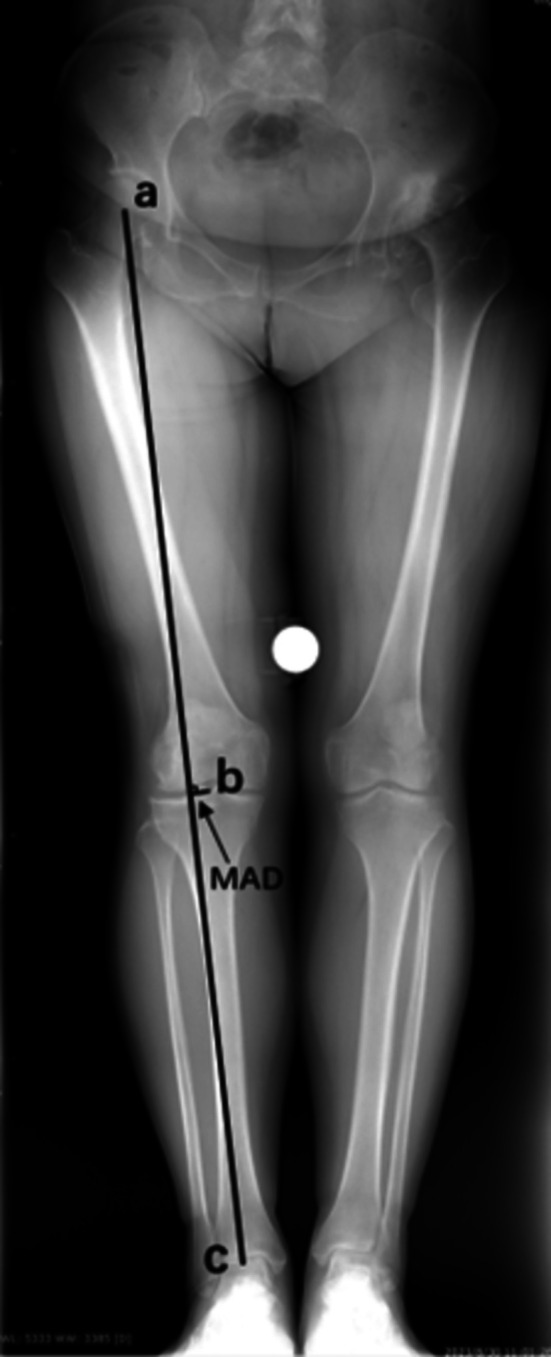

Methods: Sixty-seven patients (10 male and 57 female) with unilateral DDH in our center between May 2019 and March 2024 were retrospectively analyzed. Then, the lengths of each part of the femoral condyle were collected from CT, and the ratios of anterolateral condyle to anteromedial condyle (ALC/AMC), posterolateral condyle to posteromedial condyle (PLC/PMC), lateral condyle to medial condyle (LC/MC), anterolateral condyle to posterolateral condyle (ALC/PLC) and anteromedial condyle to posteromedial condyle (AMC/PMC) were calculated. Then, the patients were grouped by Crowe classification to further analyze the morphology of the distal femur condyle. The mechanical axis deviation (MAD) of the lower limbs was evaluated. The Pearson correlation coefficient was used to explore the correlation between knee valgus and the morphology of the femur condyle.

Result: Compared with the contralateral side, the ratio of ALC/PLC (p < 0.001) and the ratio of AMC/PMC (p = 0.031) in the ipsilateral side were significantly greater. Grouped by Crowe classification, the greater ratio of ALC/PLC (p < 0.001) in the ipsilateral side could be found in patients with Crowe III and IV DDH. The greater ratio of AMC/PMC (p = 0.003) was only found in patients with Crowe IV DDH. When the four Crowe type sides are compared with each other, the ratio of ALC/PLC in patients with Crowe III and IV DDH is greater than that of patients with Crowe I and II DDH (p = 0.005). The ratio of AMC/PMC in patients with Crowe IV DDH is greater than that of other Crowe type patients(p = 0.003). Besides, as the severity of DDH increases, the MAD increased, which was correlated with the ratio of the ALC/PLC (r = 0.609, p < 0.001) and the ratio of AMC/PMC (r = 0.229, p = 0.031).